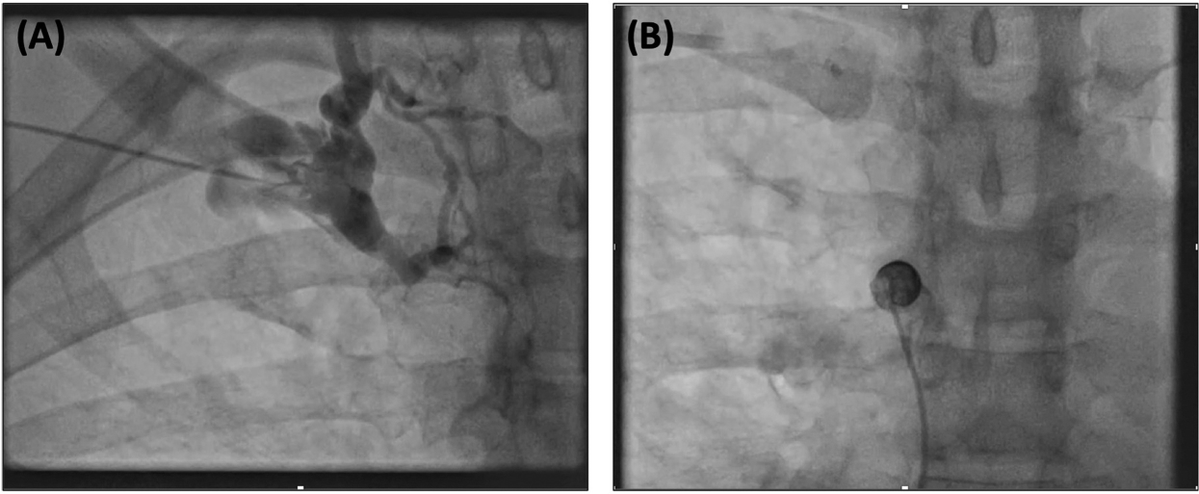

‘Inside-out’ technique to allow conduction system pacing in superior vena cava obstruction

@alphonsusliew

heartrhythmcasereports.com/article/S2214-…